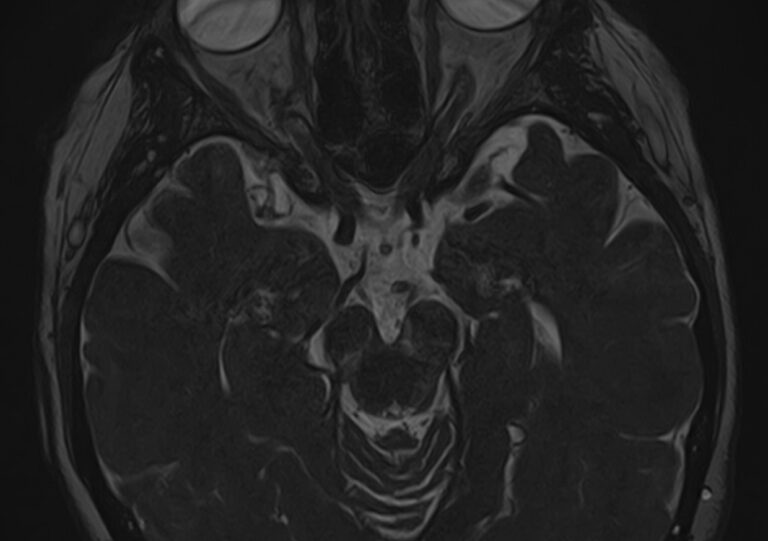

У человека в состав нервной системы входит 12 пар черепных нервов. Ядра, из которых берет начало каждый нерв, расположены в головном мозге и представляют собой скопления тел нейронов. Образованные в ядре нервные волокна выходят из черепа сквозь анатомические отверстия и далее направляются к органам чувств и мышцам. В зависимости от того, какой нерв поражен (вследствие опухоли, инфекции, травмы, воспаления, инсульта и др), происходит выпадение той или иной его функции. Это определяет разнообразие неврологической симптоматики.

Магнитно-резонансная томография позволяет детально визуализировать изменения черепных нервов и прилегающих структур. В клинике «Доступная медицина» для точной диагностики причин поражения черепно-мозговых нервов применяется новейший высокопольный 32-канальный томограф TOSHIBA VANTAGE TITAN 1,5 Тесла, который обладает высокой чувствительностью и способностью определить минимальные изменения исследуемого органа.

Признаки нарушения функций ЧМН разнообразны. Причинами поражения могут быть серьезные заболевания, которые требуют незамедлительного обращения к врачу. Для установления точного диагноза в комплексе с другими методами используют МРТ и КТ головного мозга. Оба исследования имеют свои особенности. Компьютерная томография позволяет хорошо визуализировать изменения костной ткани. На МР-изображениях лучше просматриваются мягкотканные структуры, поэтому МРТ головного мозга с прицельным осмотром черепно-мозговых нервов является методом выбора в подобных случаях.